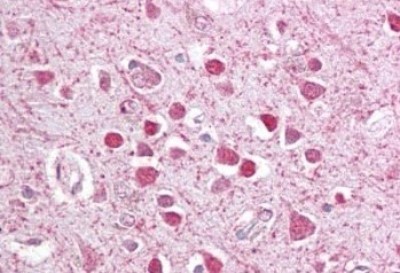

Supportive validation

- Submitted by

- Novus Biologicals (provider)

- Main image

- Experimental details

- Immunohistochemistry-Paraffin: CEBP gamma Antibody [NBP1-36944] - (2.5ug/ml) staining of paraffin embedded Human Cortex. Steamed antigen retrieval with citrate buffer pH 6, AP-staining.